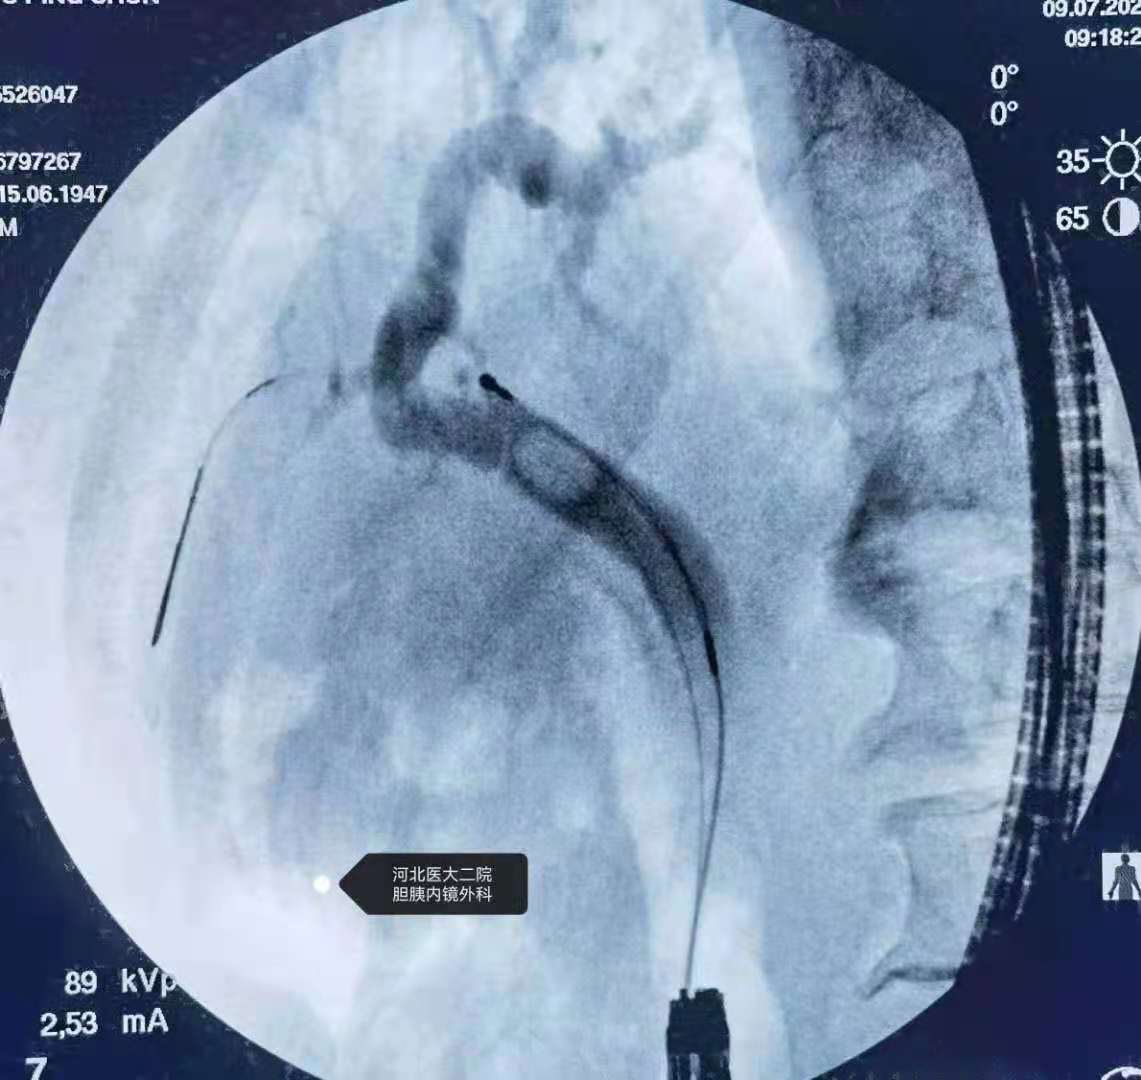

分享一例胃大部切除术后胆总管结石ERCP

上午的一例胃大部切除术后胆总管结石患者。

此类患者我们习惯应用胃镜+透明帽。

造影。

扩张。